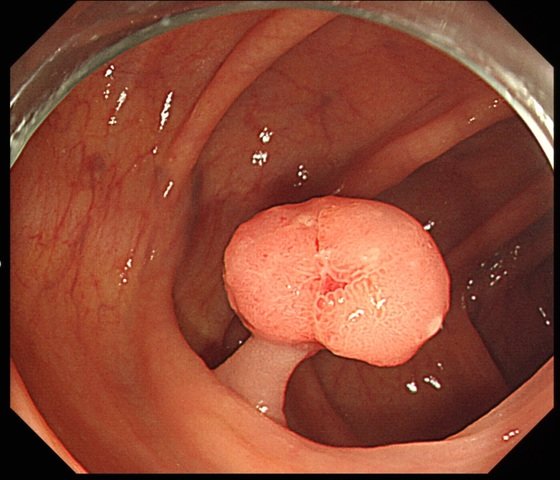

대장암은 대장내시경검사, 결장경검사 및 대변 기반 검사를통해 발견할 수 있어요. 대장내시경검사가 가장 철저한 선별검사 방법입니다. 끝에 카메라가 달린 길고 유연한 튜브를 사용하여 전체 결장과 직장을 시각화해요. 폴립이 발견되면 이 내시경이 진행되고 있는 도중에 제거할 수 있답니다.

대장암 초기증상으로 복통과 복부 불편감을 느낄수있습니다. 대장암이 발생하면 복부 부근에 속쓰림 증상이 속속 나타난다고 하고 복통이나 복부팽만감 등의 전반적인 복부에서 생기는 불편감이 주요 증상이라고 알려져 있다고 해요. 실제 조기에 대장암을 찾게된 환자의 경우 복부에 지속적인 통증을 느껴 병원을 내원하였더니 이 때 대장에서 생성한 용종을 발견함과 또한 조직검사에서 대장암을 확인해 조기에대처할 수 있었다고 합니다.